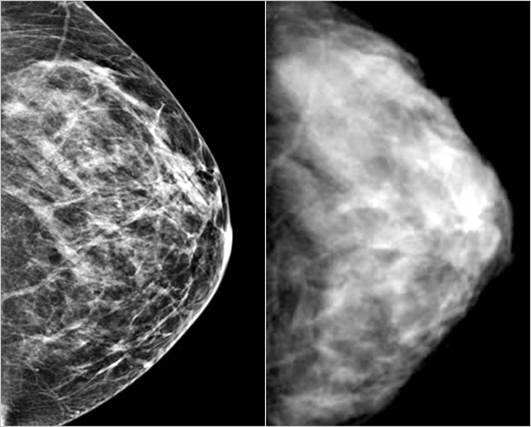

При раке молочных желез большая часть злокачественных образований образуется в молочных протоках – путей, которые позволяют молоку продвигаться из молочных желез в сосок. По замыслу врачей инъекции в сосок помогут донести необходимые для борьбы с раком препараты в область, где они бы действовали наиболее эффективно.